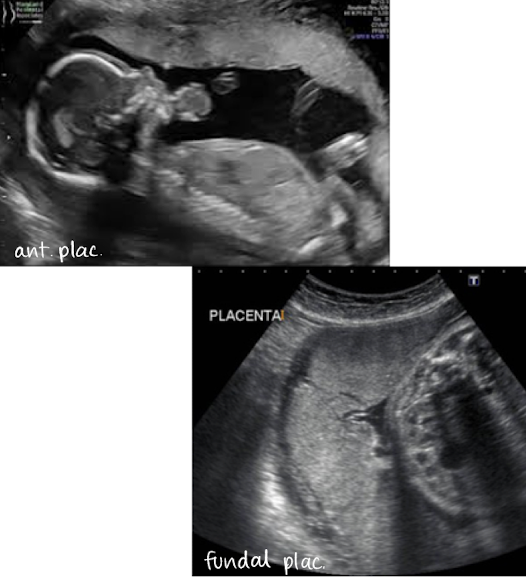

describing placental location in uterus and in relation to cervical os

in uterus

anterior

posterior

fundal (in uterine fundus)

in relationship to cervical os

close to os

away from os

covering os

if covering internal os, that is called previa